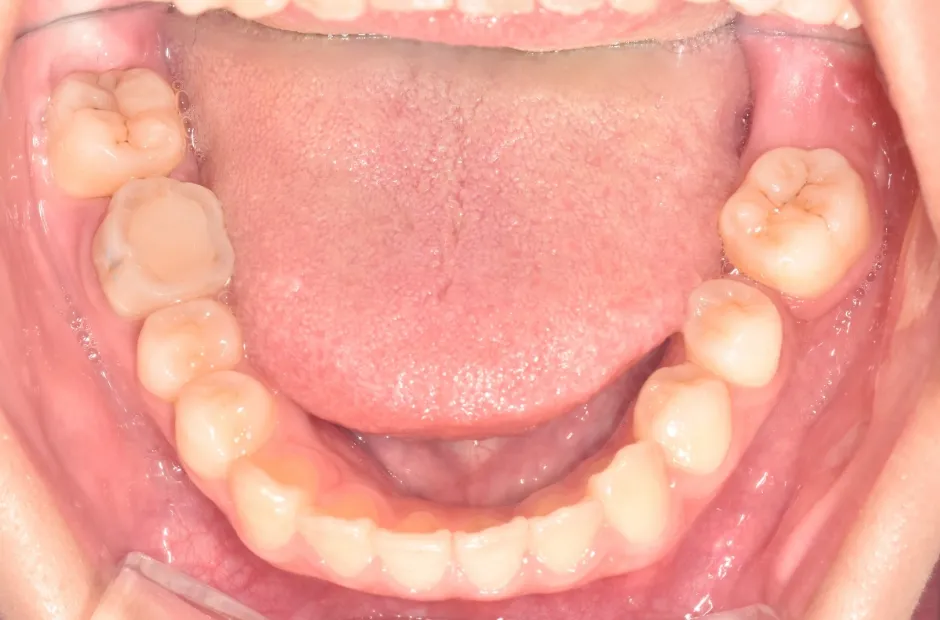

過剰歯

| 診断名・主訴 | でこぼこ |

|---|---|

| 年齢・性別 | 22歳・女性 |

| 治療期間・回数 | 1年6か月 |

| 治療に用いた主な装置 | リンガルブラケット |

| 抜歯部位 | 過剰歯 |

| 治療費 | 100万円(税抜) |

| リスク・副作用 | 装置による違和感・疼痛・歯肉退縮・歯根吸収・虫歯のリスクなど |

治療前